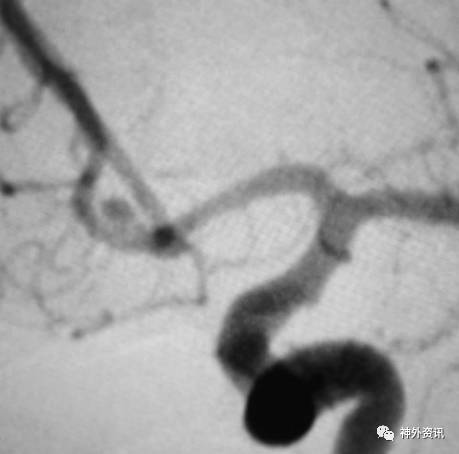

病例一

眼动脉动脉瘤,支架完全释放后,微导管成袢逆行到位

病例二

眼动脉动脉瘤,支架释放前,微导管成袢逆行到位